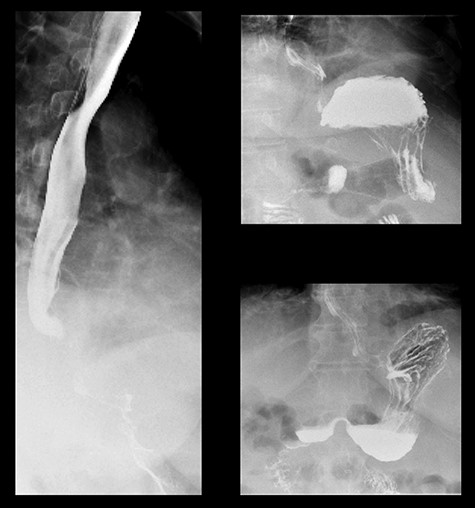

The patient was promptly brought to the theater for an exploratory laparotomy. Approximately 30 cm of ischemic small bowel segment with engorged mesentery was identified and resected; while doing so, blood clots were extruding out of the mesenteric vascular arcade. An on-table OGD was performed, demonstrating a deformed shaped stomach. The gastric band had completely eroded through the wall of the stomach. A biofilm had formed around the band device from the distal connecting tubing, tracking into the fundus of the stomach and sealing the perforation (Fig. 3). The biofilm was tracked to the stomach externally, the stomach opened and the device retrieved (Fig. 4). The stomach was closed in two layers and abdominal drains were inserted prior to closure.

Midline laparotomy demonstrating biofilm-sealed eroded adjustable gastric band.

The patient was monitored in the intensive care unit postoperatively. A focused hepatic ultrasound was performed, which demonstrated an almost completely thrombosed portal vein. The patient was, therefore, commenced on a therapeutic dose of tinzaparin sodium. The patient required intensive gastroenterology, dietician, physiotherapy and hematology input postoperatively. By 3 weeks, prior to discharge, a barium meal demonstrated normal gastric contours with no filling defects (Fig. 5). No gastric outlet emptying was observed.